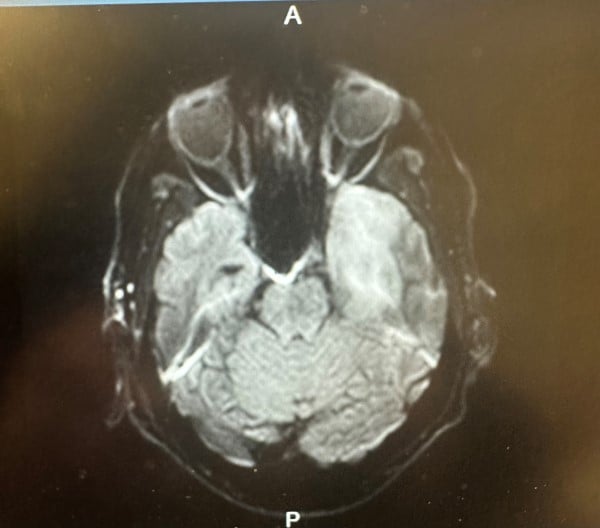

On admission, the patient was found to be somnolent, oriented only to person, with expressive aphasia. A lumbar puncture was ordered, with a meningitis panel and HSV serology. HSV-1 serology returned positive and CSF showed increased cell count, increased glucose and increased CSF protein. MRI was performed at this time, which showed mild abnormal FLAIR hyperintensity and restricted diffusion within the left medial temporal lobe cortex. Given high suspicion for HSV encephalitis, an acyclovir regimen was started.

- (MRI) brain is also used to assess signs of temporal lobe involvement, which supported the diagnosis. Brain MRI would also eliminate other alternative causes of mental status changes, such as brain abscess.